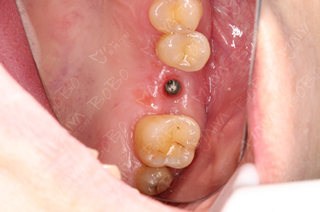

医生为许女士采取德国种植牙方案

植牙模拟判断咬合程度